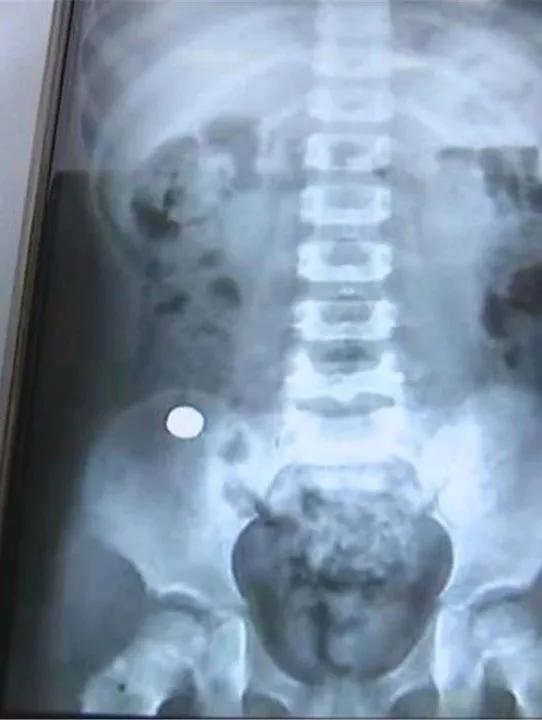

事发后,他们曾经在内蒙古当地医院给孩子拍了CT。异物形状小而圆,大家怀疑很可能是一枚纽扣电池。

家长告诉医生,CT照片显示,异物已经进入到肠道,但孩子没有明显的食欲减退、腹痛症状,因此当地医生建议先观察一下,等待异物自然排出。可6天过去了,异物几乎没有任何移动,家人才着急起来。

长春市儿童医院 消化内科 副主任 罗磊:通过结肠镜做这个手术。我们达到回盲部,也就是小肠和大肠交界处,发现了此异物,但并不是纽扣电池,是一个黑色的磁铁。

医生告诉记者,因为回盲部比较狭窄,正因为磁铁卡在了这个位置,所以未能顺着肠道排出。磁铁停留的这6天,由于异物摩擦,孩子的回盲部已经出现了充血、水肿和糜烂,如果磁铁再不及时取出,很有可能引起内脏损伤、肠道穿孔等并发症。